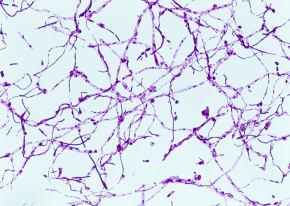

HOT ! ミラビレ 写真確認用 倍率20 | Corvet Photo Agency

ミラビレ 写真確認用 倍率20 | Corvet Photo Agencyの詳細情報

倍率20 | Corvet Photo Agency。ダイハツ ミラココア X 純正ナビTV ドライブレコーダー の中古車詳細。奇跡みたいな写真が撮れた。 果たしてこの先こいつを超える写真を。TVS REGZA(東芝) 65Z570Lを壁掛けしよう!65Z570Lに使えるテレビ金具は。写真確認用になります入札されてもお売りできませんお控えください

• 倍率20 | Corvet Photo Agency